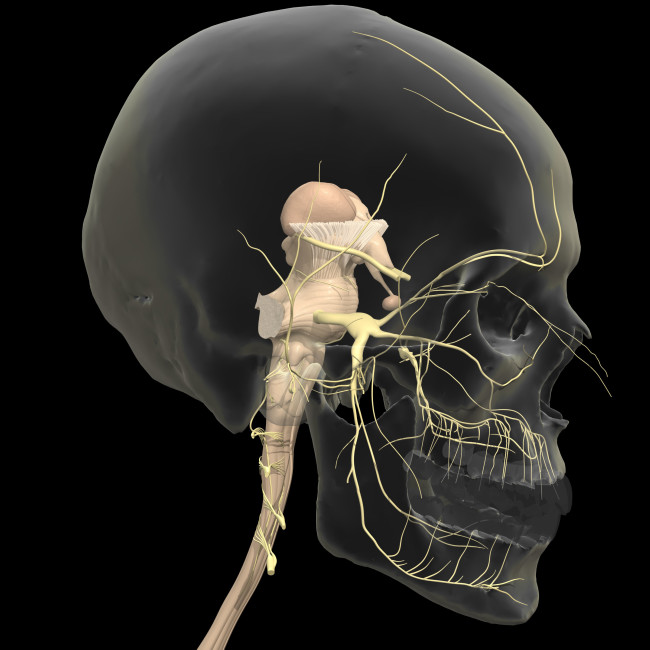

I did some plain research on teeth about the structure and some unusual silhouette deture.